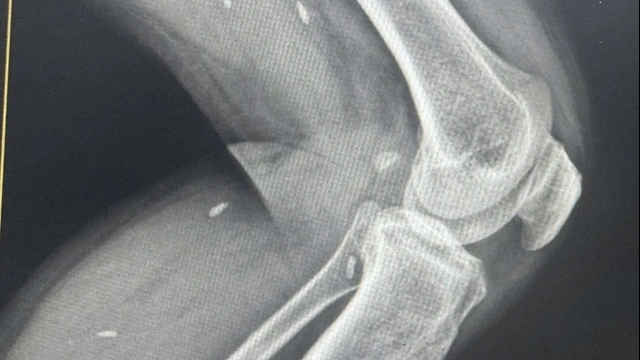

| Nhân viên y tế lấy mẫu xét nghiệm tầm soát SARS-CoV-2 |